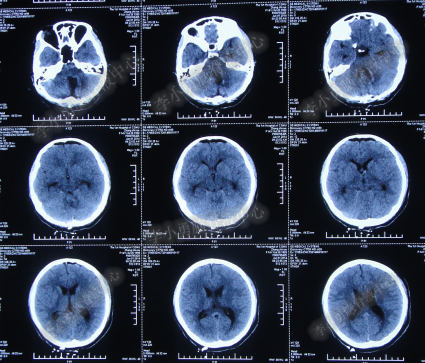

腰大池持续引流20天内,体温仍间断高热,曾3次脑脊液细菌培养均示鲍曼不动杆菌,先后使用利奈唑胺+克倍宁,利奈唑胺+克倍宁+奥硝唑,舒普深+米诺环素+来立信+氟康唑,舒普深+米诺环素+美罗培南+氟康唑,及日达仙、人免疫球蛋白提高免疫力,但颅内感染仍控制不住,期间多次头部CT检查均示脑室无明显扩张(图-7、图-8、图-9)。

图-7:2014年6月9日头部CT

图-8:2014年6月14日头部CT

图-9:2014年6月21日头部CT